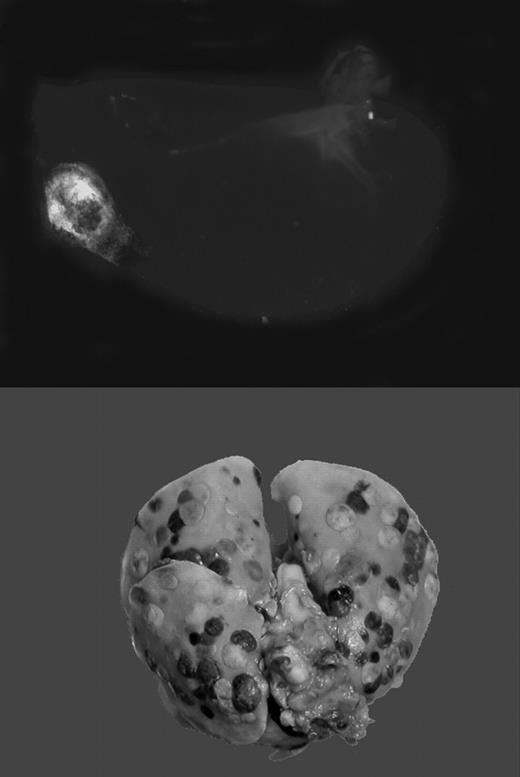

Tumor cells travel through blood or lymphatic vessels to secondary organs, where they exit the vascular compartment to form metastases. This route of tumor dissemination through the bloodstream has been termed hematogenous metastasis. The level of tumor-associated procoagulant activity correlates directly with metastatic potential, and forced expression of the initiator of blood coagulation, tissue factor (TF), is sufficient to confer metastatic potential onto tumor cells.1 In animal models, metastasis can be effectively suppressed by genetic disruption or pharmacologic inhibition of the coagulation system or platelet activity. Using genetically altered mice lacking fibrinogen, Palumbo and colleagues previously demonstrated that absence of fibrinogen markedly reduces the formation of pulmonary and lymph node metastases, without affecting growth of the primary tumor.2 Recent work by Camerer and colleagues3 confirms this finding, and, in addition, showed that platelets are also necessary for successful hematogenous metastasis. Importantly, attenuating platelet responsiveness to thrombin suppressed metastasis to a similar extent as the complete absence of platelets, or the lack of fibrinogen. Together, these studies clearly established that metastasis of circulating tumor cells requires TF-initiated coagulation on the surface of tumor cells, which promotes thrombin generation, fibrin formation, and platelet aggregation. However, it remained obscure how this chain of events translates into an enhancement of metastasis.FIG1

Gαq deficiency dramatically diminishes the metastatic potential of circulating tumor cells. See the complete figure in the article beginning on page 178.